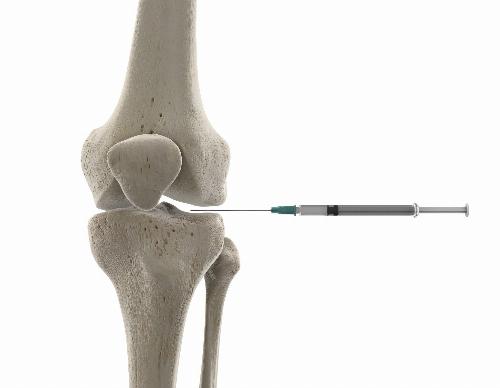

L’infiltration consiste à injecter un traitement directement dans l’articulation ou autour d’un tendon, sous contrôle échographique.

Arthrose du genou (gonarthrose)

Épanchement articulaire du genou

Infiltration ciblée du traitement